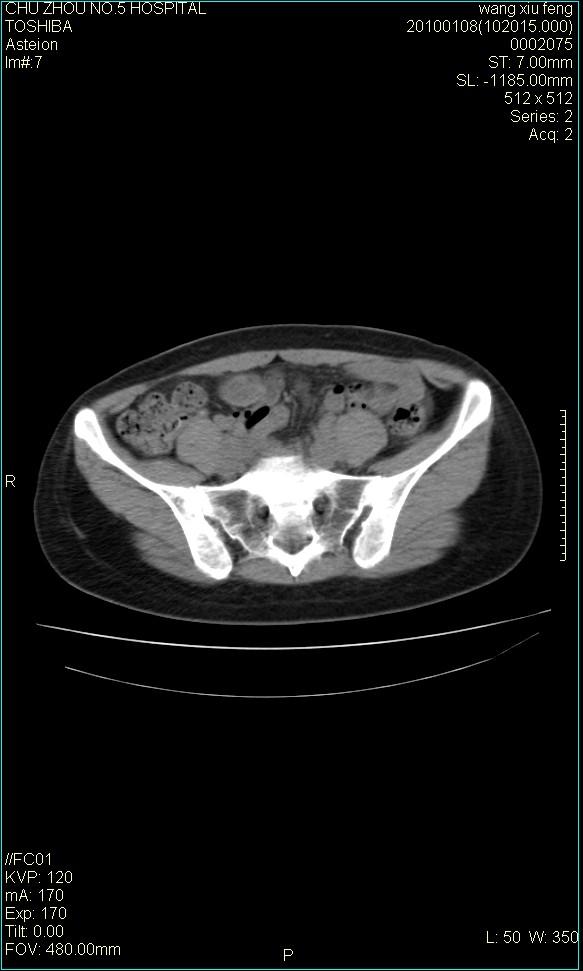

标题: CT24042:子宫右上方囊性包块,性质???? [打印本页]

标题: CT24042:子宫右上方囊性包块,性质????

f-41,左乳腺ca术后4年,b超示:子宫右上方囊性包块约5.5*3.4cm,前日行胸部ct平扫未见明显异常。